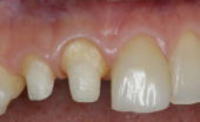

- グラスファイバー系コアは、光の透過性が象牙質に極めて近く、歯質に近似した色をもちます。

- 透明感のある自然な色調を得ることができます。

- 歯根の変色や歯肉へのメタルタトゥーを防止することができます。